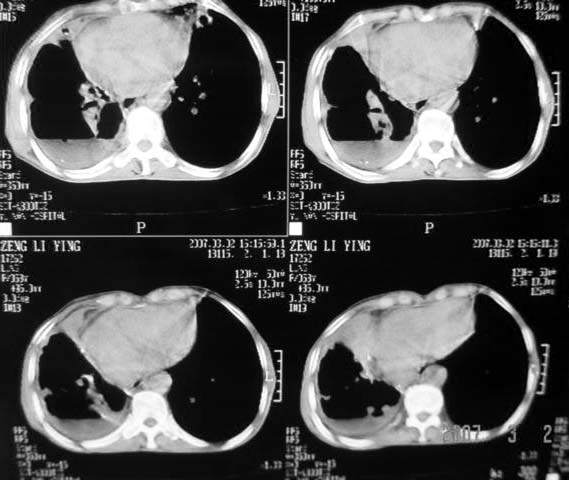

以下是引用dyqct在2007-3-2 22:04:00的发言:[br]考虑:1、右侧毁损肺伴支气管胸膜瘘(多条支气管与胸腔相通、液气胸);[br] 2、左肺浸润型肺结核。[br][br][br][br]